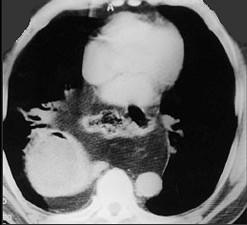

问题 女,43岁,急性胸骨后剧痛,腹痛腹胀、呕吐,影像检查如图,最佳的诊断是 ( )

选项 A.后纵隔神经源性肿瘤 B.右下肺癌 C.食管裂孔疝并胃扭转 D.后纵隔畸胎瘤 E.后纵隔脓肿

答案 C